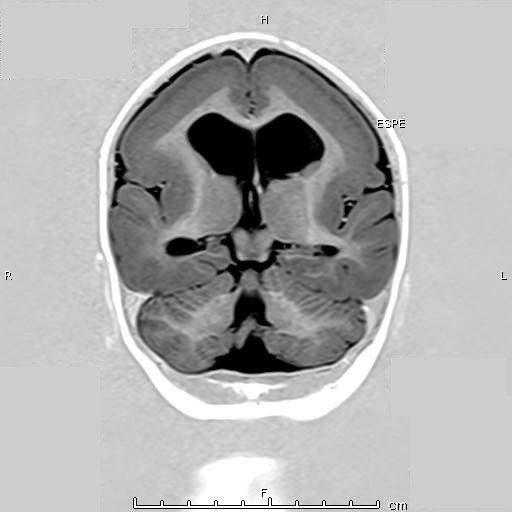

Características de Imagens

A lisencefalia inclui uma variedade de malformações cerebrais graves, incluindo agiria (giro ausente), paquigiria (giro amplo) e heterotopia de banda subcortical. Na lisencefalia (que significa literalmente cérebro liso), a superfície do cérebro parece lisa. Pode ocorrer isoladamente ou em associação com outras síndromes (síndrome de Miller-Dieker).

O exame do cérebro na lisencefalia tipo I mostra um córtex cerebral com quatro camadas em vez de seis camadas, como em pacientes normais, enquanto na lisencefalia tipo 2 o córtex cerebral é desorganizado e parece enrugado ou nodular devido ao deslocamento completo do córtex cerebral com agrupamentos de neurônios corticais separados por tecido glio-mesenquimal. Os pacientes também apresentavam anormalidades musculares e oculares.